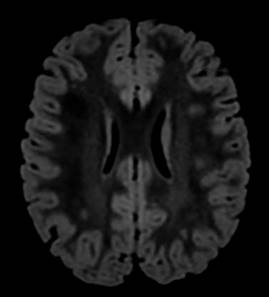

Se trata de paciente femenino de cinco años de edad que ingresa al Servicio de Urgencias en el Hospital Angeles México con signos vitales en parámetros normales, presenta mioclonías focalizadas en miembro torácico derecho, emesis, atetosis y relajación de esfínteres. En urgencias presenta nuevamente crisis focalizadas en el miembro torácico derecho. En hospitalización persiste con crisis convulsivas refractarias a tratamiento. Se realizan paraclínicos (hemocultivo y hemograma) y se recaba electroencefalograma (EEG) y resonancia magnética (RM), la cual muestra cambios morfológicos, leucoaraiosis (Figura 1) y alteraciones vasculares (Figura 2). Posteriormente, se realiza punción lumbar con presencia de anticuerpos anti-NMDA y tomografía por emisión de positrones y tomografía computarizada que muestra hipometabolismo severo en sistema nervioso central. Ingresa a UTIP para sedoanalgesia, plasmaféresis y aplicación de inmunoglobulina intravenosa e inmunomoduladores.

Figura 1: Resonancia magnética en secuencia FLAIR con zonas de hiperintensidad de señal en la sustancia blanca supratentorial a nivel periatrial con extensión periventricular y subcortical de predominio hipocampo-periatrial con mayor acentuación en el lado izquierdo. En relación con zonas de leucoaraiosis de tipo inespecífico.